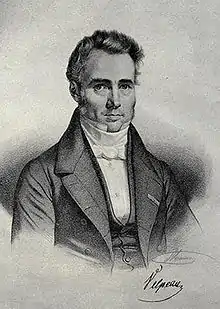

La première description dans la littérature médicale d'un cas de leucémie remonte à 1827. Alfred Velpeau décrivit le cas d'un fleuriste âgé de 63 ans atteint d'une maladie et présentant fièvre, fatigue, des calculs rénaux et une importante dilatation du foie et de la rate. Il observa que le sang du patient avait une consistance de gruau et postula que cette apparence pouvait être causé par des particules blanches[76]. En 1845, une série de cas de patients décédés avec des rates dilatées et des « changements de couleur de consistance de leur sang » fut rapporté par le pathologiste J.H. Bennett ; il emploie alors le terme « leucocythémie » pour décrire cette affection[77].

Le mot « leucémie » fut employé pour la première fois par Rudolf Virchow, médecin pathologiste allemand, en 1856. Il décrivit, grâce à un microscope, un excès de globules blancs chez des individus présentant les symptômes décrits par Velpeau et Benett. Virchow ne connaissant pas l'origine de cette anomalie, il la nomma par un terme purement descriptif leucémie (en grec : sang blanc)[78].